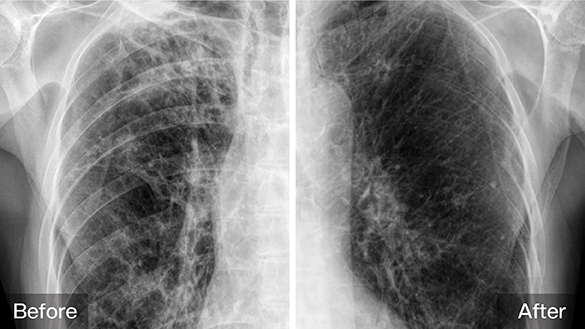

Bone Suppression

Enhances soft tissue visualization for superior chest X-ray training.

Image Processing

Post-digital image optimization that enhances clarity, contrast, and consistency for reliable diagnostic interpretation.

Scatter Reduction

Scatter reduction processing simulates clinical image quality by minimizing scatter effects and enhancing contrast.